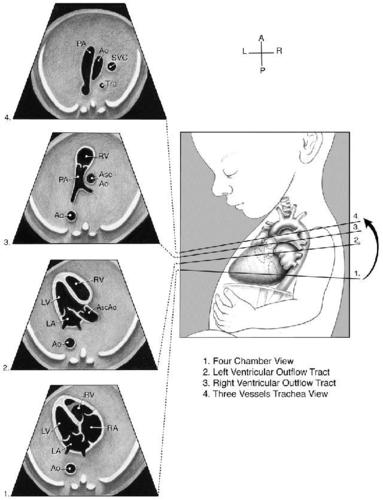

充分理解胎儿三血管气管切面(正常篇)

让我们一起再复习一下三血管气管切面在胎儿心脏疾病诊断的价值(1)

三血管及气管切面 短轴切面(心室及流出道) 主动脉弓 导管弓 上腔静脉

三血管气管切面示意图

三血管气管切面